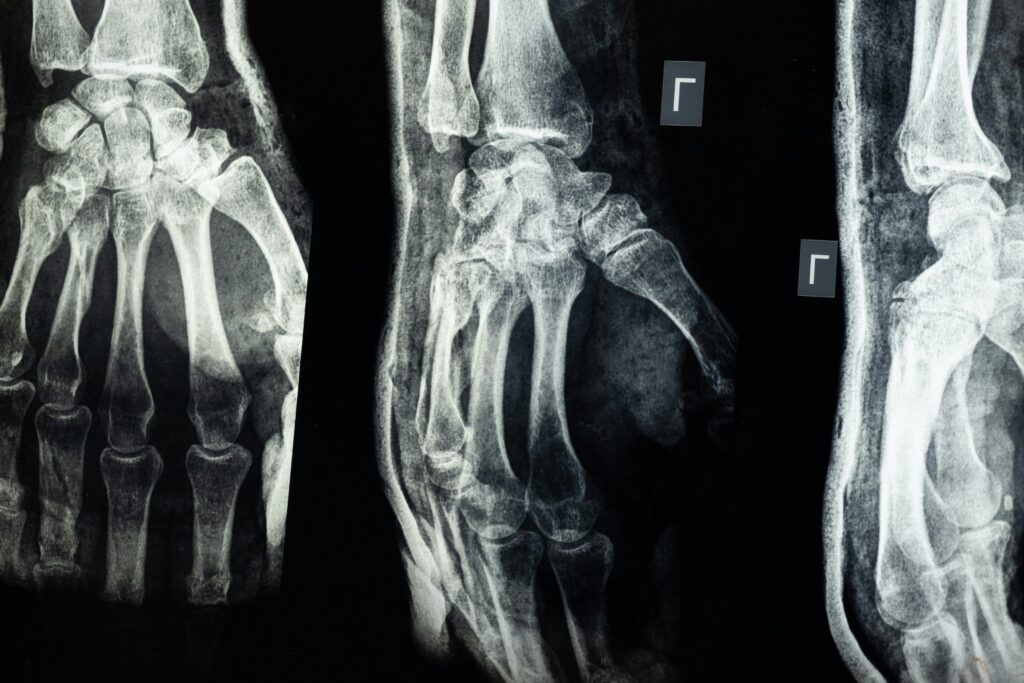

最近湊巧連續遇到幾個骨裂的患者,調整完後,

一般骨裂的患者,因為在結構沒有還原的情況下,

只要隨著肢體的挪移、

就會透過肌肉或是結締組織去牽拉到附著點的骨頭,

這樣的應力作用在結構完整性被破壞的骨頭上,

就會造成明顯的疼痛,